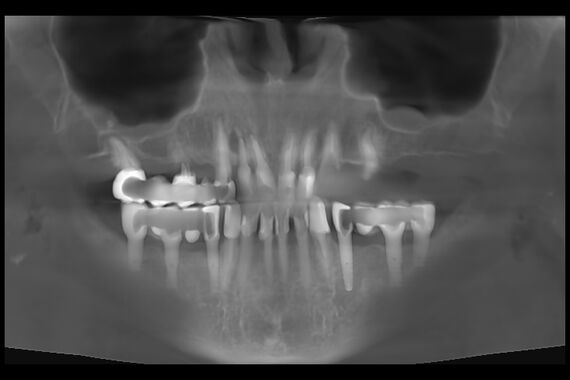

Кейс №5 - Установка 6 имплантов и несъемного протеза за 4 дня

02 Сентября 2020 Установка протеза по методике All-on-6

Решение

На очной консультации после обследования полости рта и изучения данных 3D-исследования челюстей совместно с пациенткой был выработан план реабилитации верхней челюсти с использованием современной и эффективной методики протезирования All-on-6 (все на 6-ти).

Была проведена операция на верхней челюсти, во время которой:

• удалены несостоятельные металлокерамические протезы зубов,

• удалены разрушенные корни и все имеющиеся очаги воспаления,

• установлены 6 имплантатов,

• в последующие 4 дня изготовлен и зафиксирован несъемный эстетичный и функциональный протез.